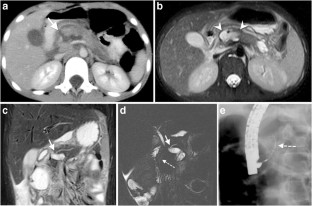

Of 3,265 patients presented as trauma team activations during the study period, only 28 (0.86%) children (19 boys, 9 girls; mean age: 7.14 years; age range: 1–15 years) had pancreatic injury. Of the available 27 CTs of the abdomen, 26 were performed on the day of trauma. Associated injuries were seen in 25/27 children, most frequently in the liver and lung, 16 (59.2%) each. There were 5 (19%) Grade I, 9 (33%) Grade II, 8 (30%) Grade III and 3 (11%) Grade IV. No patients had Grade V injury. No pancreatic parenchymal injury was identified in 2 (7%) patients with isolated fluid around the pancreas and mesentery. The pancreatic duct was visible in all 10 children (days: 0–330, median days: 41 post-trauma) who had MRI. Eight of these children, who had Grade III/IV injuries on CT and confirmed pancreatic duct injury on endoscopic retrograde cholangiopancreatography (ERCP) or surgery, showed either signal intensity difference in pancreatic parenchyma and/or caliber difference in the pancreatic duct proximal and distal to the injury site. Two patients died because of multiorgan injuries, 9 patients (mainly with Grade III and IV injuries) underwent surgery and/or ERCP, and 16 patients were managed conservatively. AAST grading of pancreatic injury on CT correlated with type of management (P=0.0001) with most of the Grade III and IV injuries treated with intervention and/or surgery while all of the Grade I and II injuries were treated conservatively.

Pancreatic injury is rare in children but often associated with other organ injuries most frequently involving the liver and lung. CT grading of injury correlates with management and guides intervention and/or surgery versus conservative treatment. MRI is useful for assessing pancreatic duct injury by demonstrating the pancreatic duct directly and/or secondary changes like signal intensity difference in pancreatic parenchyma and caliber difference in the pancreatic duct.

Fig. 1